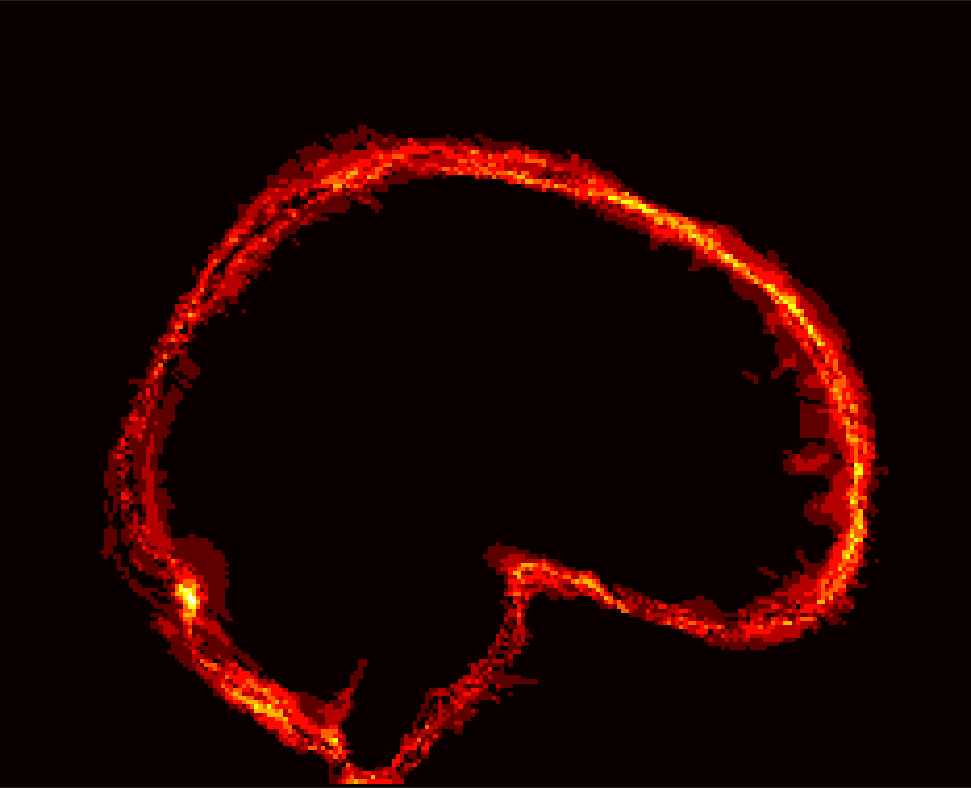

Fig. 1 shows example images from each dataset to illustrate image variability. IBSR and LPBA40 contain images from normal subjects and include large portions of the neck; BRATS has very low out-of-plane resolution; and the TBI dataset contains large pathologies and abnormal skulls.

Refer to caption

Figure 1: Illustration of image appearance variability on a selection of images from each (evaluation) database. From top to bottom: IBSR, LPBA40, BRATS and TBI.